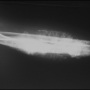

- Periosteal Osteosarkomlar

Kemik çevresindeki zardan kaynaklanan osteosarkom tipidir. Bu da sıklıkla düşük derecelidir ve emniyetli sınırlarla çıkartılması gereklidir.

örnek-1  Periosteal osteosarkomlar - 1